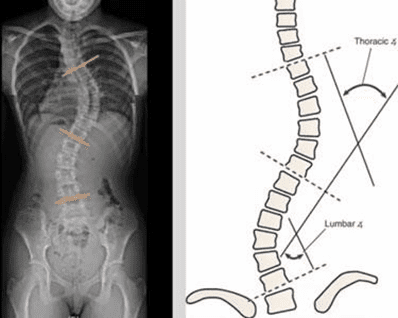

Is scoliosis becoming more common as you age? The answer is “yes” in age degenerative scoliosis (ADS) Research shows an increase in the number of geriatric diseases in aging populations around the globe. Specifically, there are more older people getting diagnosed with ADS. While scoliosis can be diagnosed as idiopathic, some research suggests that it […]